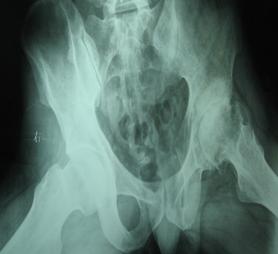

股骨头坏死是一种常见的骨科疾病,又叫股骨头缺血性坏死。目前股骨头坏死的治疗方法比较的多样,不管是什么方法,都能够很好的缓解病情,甚至达到自愈的目的的。股骨头坏死的病因有很多,所以治疗也需要针对病因对症治疗,才能很好的达到预期的效果。那么,下面一起看看股骨头坏死的常见病因有哪些?

1、创伤因素:创伤是导致股骨头坏死的主要原因之一。如外力撞击引起股骨颈骨折、髋关节脱位、髋关节扭挫伤等。创伤是造成股骨头坏死的主要因素。但创伤性股骨头缺血坏死发生与否、范围大小,主要取决于血管破坏程度和侧支循环的代偿能力。